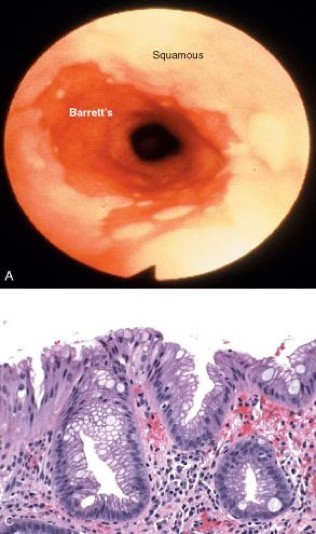

A 55 year old man has had chronic heartburn for the last 20 years that he has “managed” with tums and decreasing ingestion of spicy foods. Upon endoscopic examination, you see the following. What is his diagnosis and what other concerns might you have?

Barrett’s esophagus= Endoscopically recognizable columnar metaplasia of the esophageal mucosa that is confirmed pathologically to have intestinal metaplasia, the latter defined by goblet cells. Complication of longstanding reflux

Both the endoscopic and pathologic components should be present to establish BE

See “salmon pink tongues” (columnar metaplasia) and goblet cells in luminal esophagus= intestinal metaplasia

Below: contrast with normal GE junction: Barrett’s squamocolumnar junction (Z-line) does not correspond to gastroesophageal junction

Development of adenocarcinoma in BE= metaplasia–> dysplasia–> carcinoma sequence (50-fold increase in adenocarcinoma- 5-8% 5-year survival)

* 2% risk in BE pts W/O dysplasia

* 20% risk in BE pts W/ high-grade dysplasia (~45% low-grade dysplasia progress to high grade)